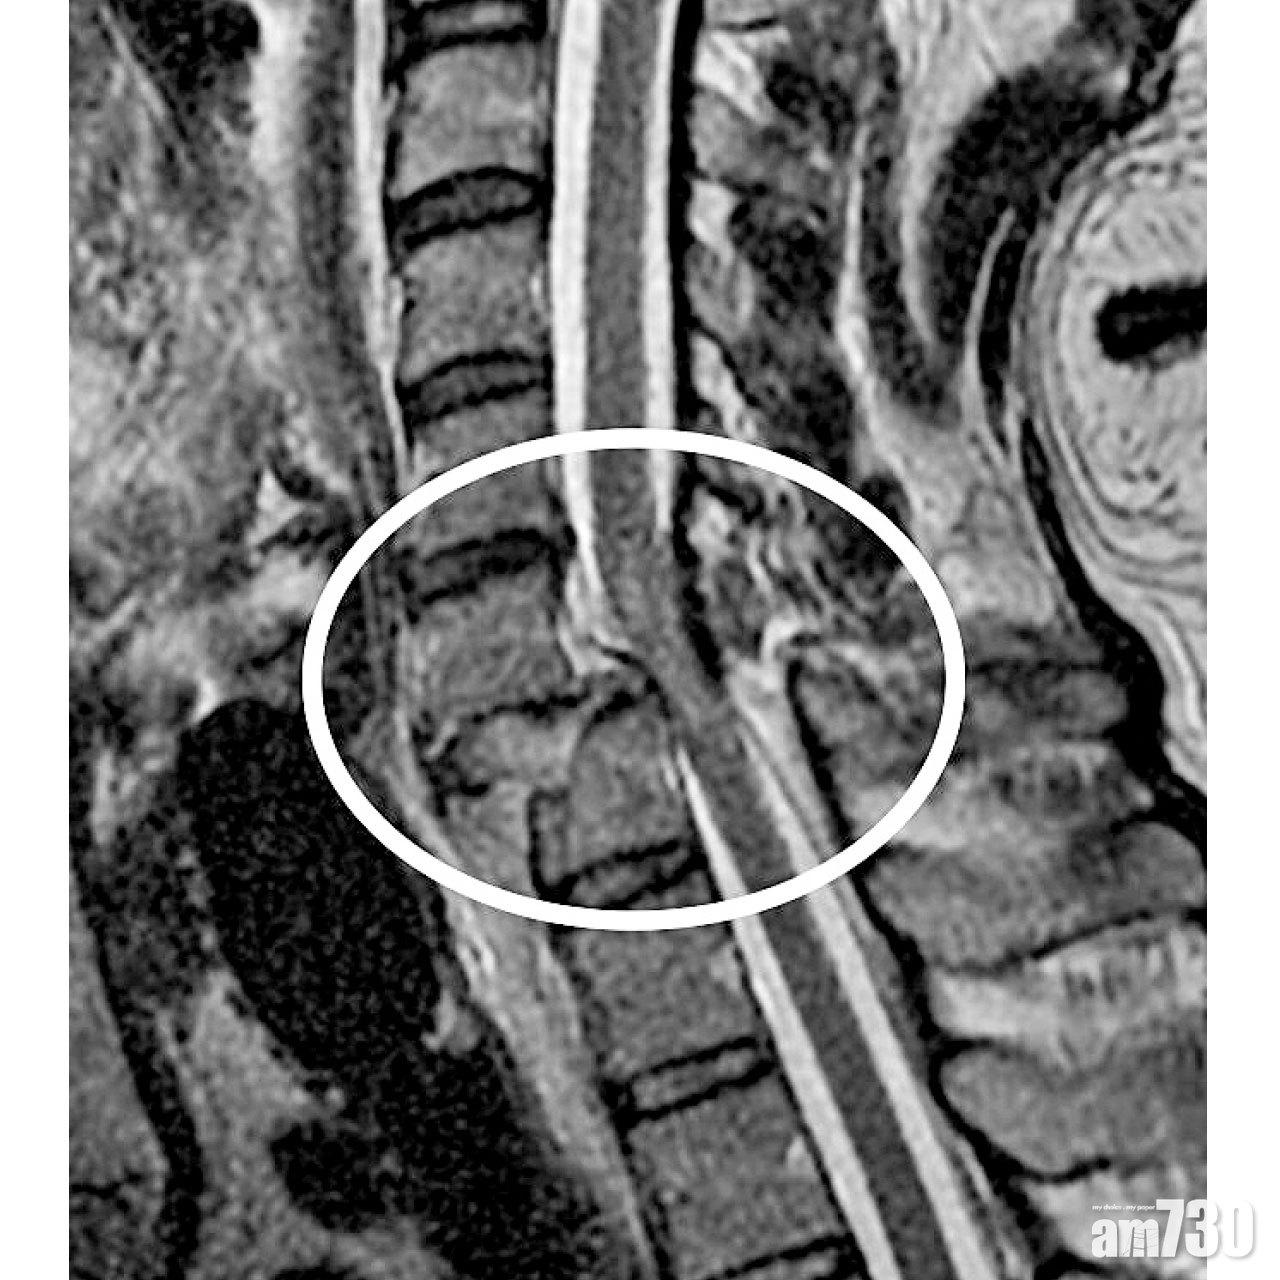

當傷者的生理機能穩定下來,骨科醫生會盡快安排照磁力共振來評估傷勢,並做頸椎減壓及融合術。頸椎骨折得以固定後,傷者便可盡快離床接受復康治療,免得臥床日久,帶來肺炎或褥瘡等可致命的併發症。醫學界至今仍未研發出,能令脊髓完全損傷者恢復運動功能的治療。雖然外骨骼機械人技術,能輔助傷者站立與行走,但因價格高昂而仍未普及。至於脊髓非完全損傷者,四肢肌力都會在術後首年內,在復康治療下有所改善。部分傷者可以重新站立行走,或是操控電動輪椅,自由地出入社區。